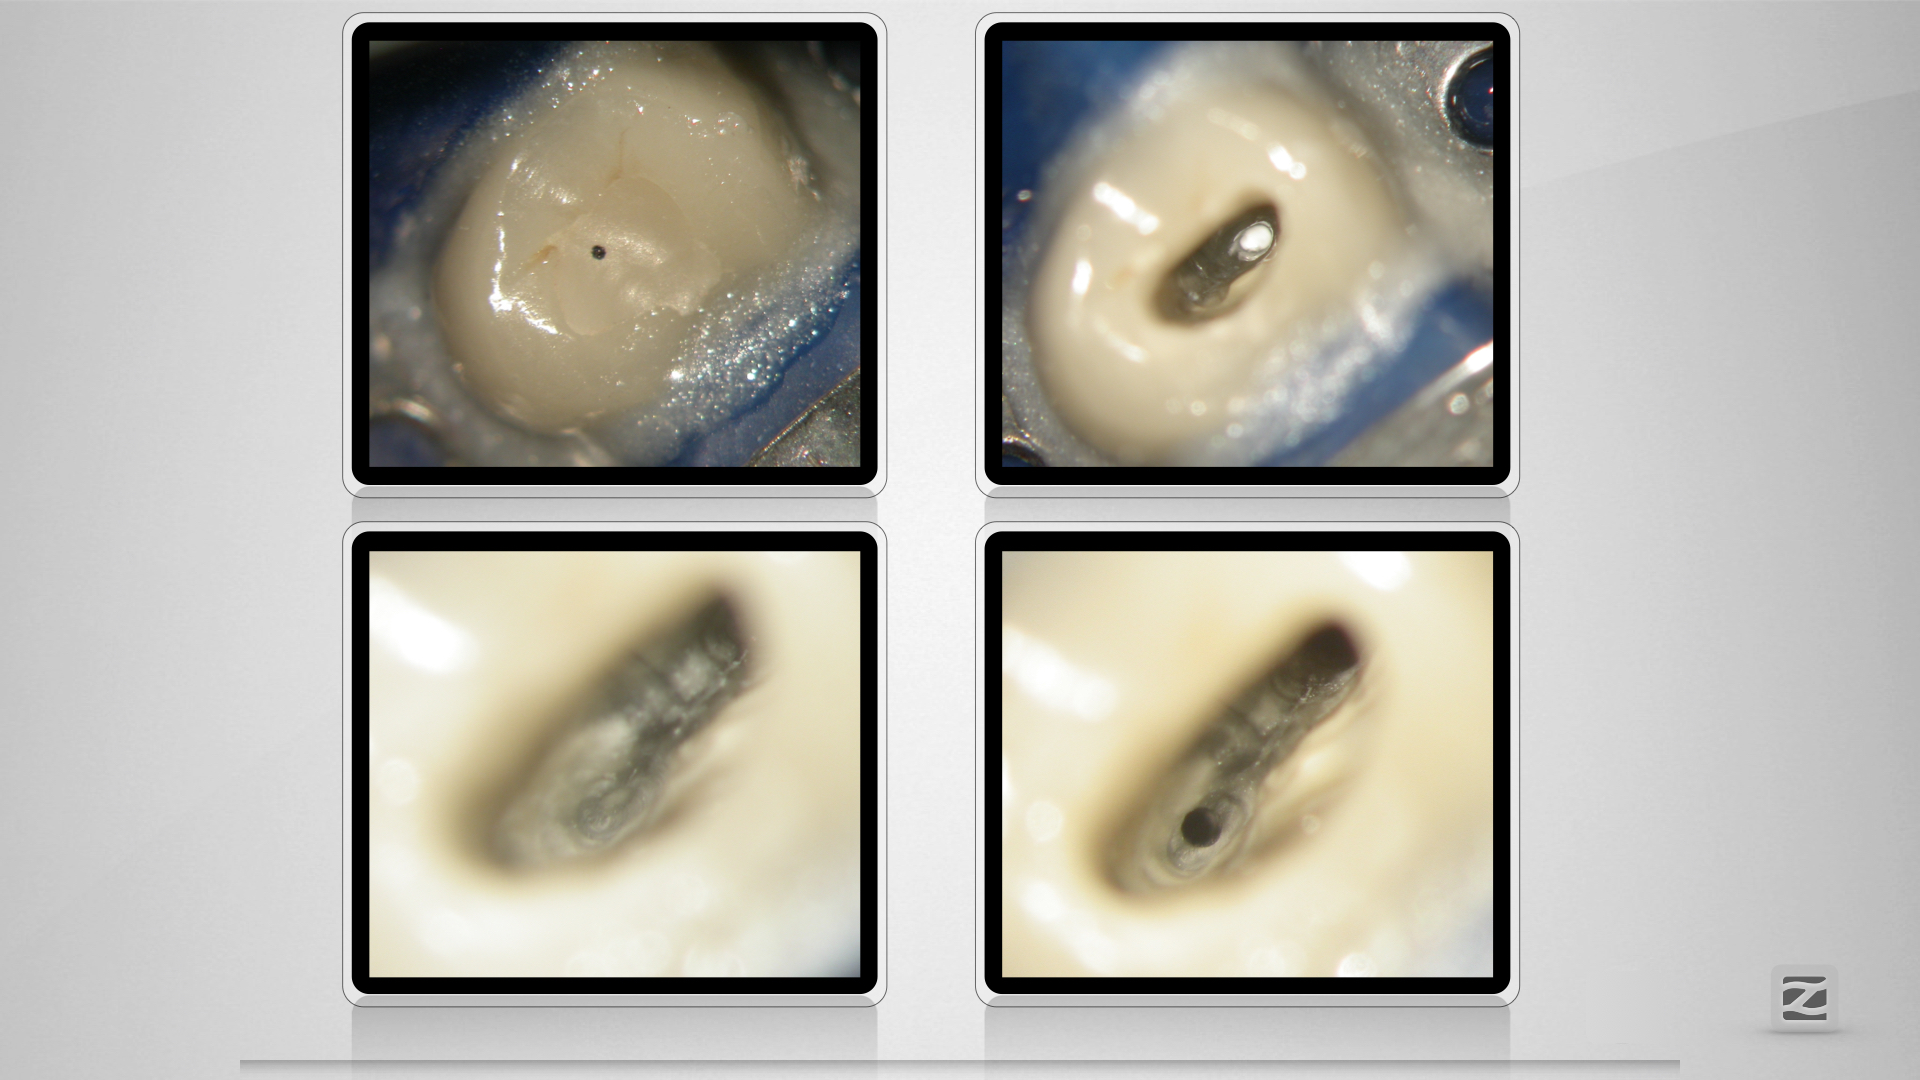

14D.008

Dummheit gehört bestraft.